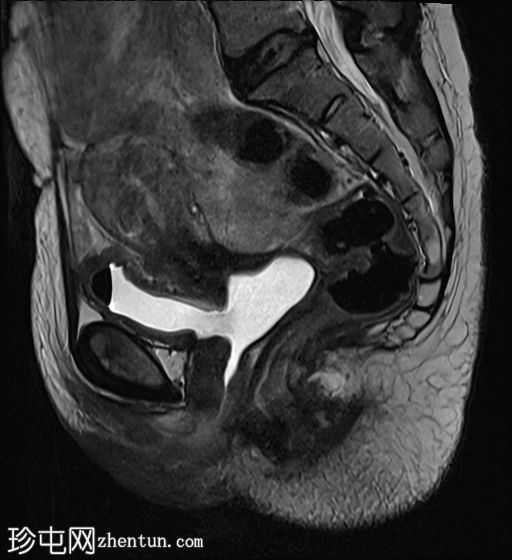

膀胱充盈后

MRI

矢状位

T2加权像

膀胱后壁与阴道前壁之间存在宽阔的瘘管。膀胱内可见气液平面。

阴道后穹窿上部与直肠中段前壁之间可见另一条较小的瘘管。在重扫描T2加权像上也可见。

子宫未见局灶性病变。

左侧卵巢可见液性囊肿。

盆腔少量游离液体。